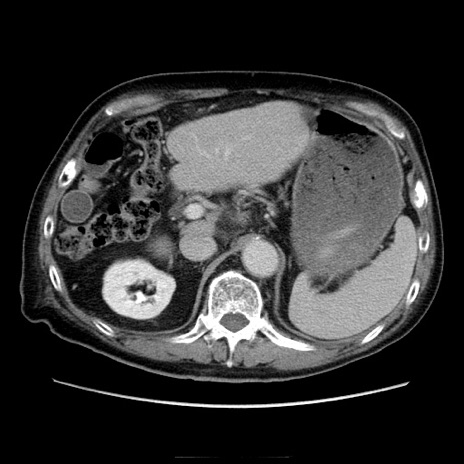

症例21(横断像)

【症例】70歳代男性

【主訴】腹痛

【現病歴】肝硬変・肝細胞癌にてかかりつけの方。約9時間前に食後より腹痛出現。症状が徐々に増悪し、嘔吐出現したため来院。

【既往歴】肝硬変、肝細胞癌(RFA、TACE後)

【身体所見】意識清明、表情苦悶様、BT 36℃、BP 129/78mmHg、P 88bpm、SpO2 97%(RA)、右上腹部から心窩部にかけて圧痛あり、反跳痛なし、筋性防御あり。

【データ】WBC 5800、CRP 0.16